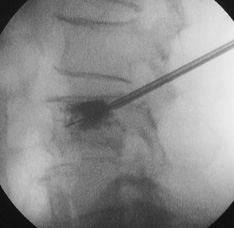

皮下局麻的情况下使用3mm的探针插入压迫的锥体内,再放入骨水泥。30分钟即可完成手术次日便可出院。

术中随时拍下X光照精确确认骨折的部位

放入之前的骨水泥成2cm细长状,注入后便膨大便圆球状,使其把压迫得锥体从内部支撑起,使其稳固